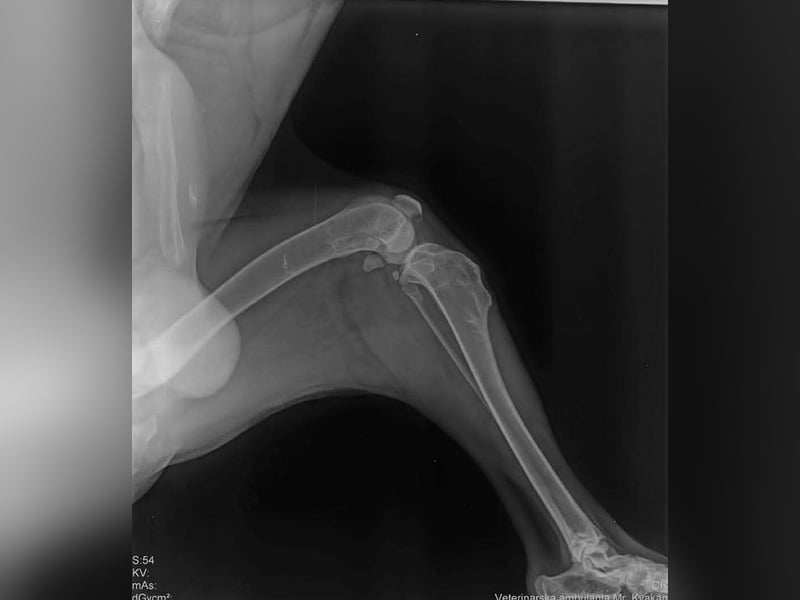

Bemerkungen: Marli hatte eine OP am Knie

Marli kam aus einer Romasiedlung. Er konnte nicht richtig laufen. Der Tierarzt stellte eine alte Knieverletzung fest die dann umgehend operiert wurde. Alles ist sehr gut verheilt und heute genießt Marli sein neues Leben.